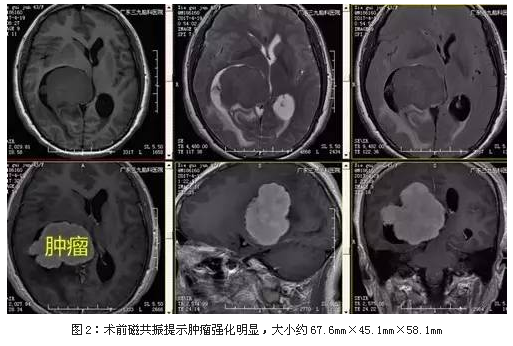

入院后完善术前相关检查,磁共振提示肿瘤强化明显,大小约67.6mm×45.1mm×58.1mm,术前CTA检查示肿瘤血供行全麻下右侧脑室内占位病变切除术,手术由神经外一科主任张良主刀完成,术中肿瘤全切,术后恢复良好。

侧脑室脑膜瘤影像学检查主要依靠头部CT及MR,CT表现为侧脑室(常见三角区) 病灶呈类圆形或分叶状,边界清楚;平扫呈略高密度影,增强扫描呈均匀强化,可有钙化灶, 侧脑室常有不同程度扩大,MRI可了解肿瘤的解剖位置以及与周围重要结构的毗邻关系,TWI呈等信号或略低信号,T 1 WI呈略高信号或等信号;增强扫描有明显的均匀强化或不均匀强化。本例CT示右侧侧脑室一团块状稍高密度影,边界清楚,未有钙化,MR呈长T1偏等T2异常信号,增强后明显强化,侧脑室病灶周围示片状水肿信号影,左侧侧脑室轻度扩大,中线结构左偏。